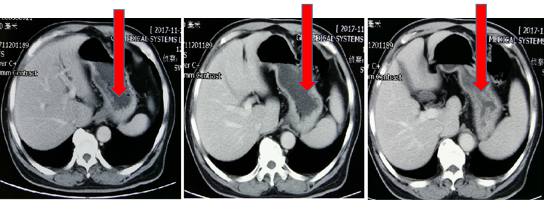

2018-11-05加入S1单药化疗,6次靶向+2周期S1化疗后,肿瘤标记物下降:CEA 947ug/L → 23.5ug/L血常规恢复正常。肿瘤明显缩小,范围变少。ECOG 1分

图3

病灶缩小,疗效评价:PR